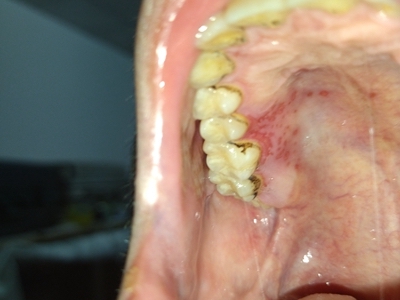

口腔带状疱疹口腔溃疡图

口腔带状疱疹黏膜症状为上腭起了密密麻麻的淡红色溃疡,散在或簇集状分布,针尖至粟粒大小,部分损害相互融合成片,与周围黏膜界限清楚。